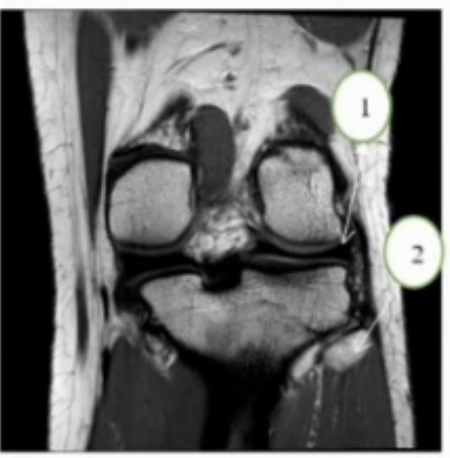

Key for 23-24 A medial meniscus B. lateral meniscus C. Tibia D. Fibula

Where is Fibula located in relation to the Tibia in coronal view?

a. Anterior

b. Posterior

c. Lateral

d. Medial